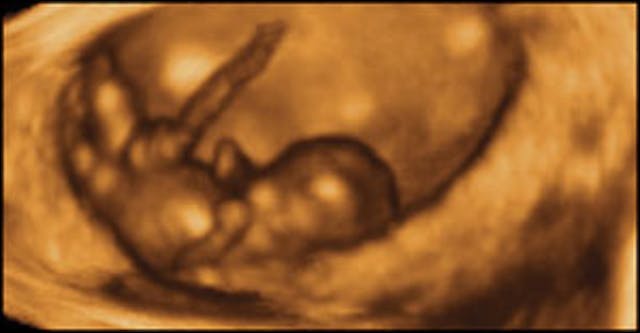

“At 8 weeks, this baby can kick and straighten his legs, and move his arms up and down.” This and other incredible 4D ultrasound photos can be found here – copyright of Life Dynamics.